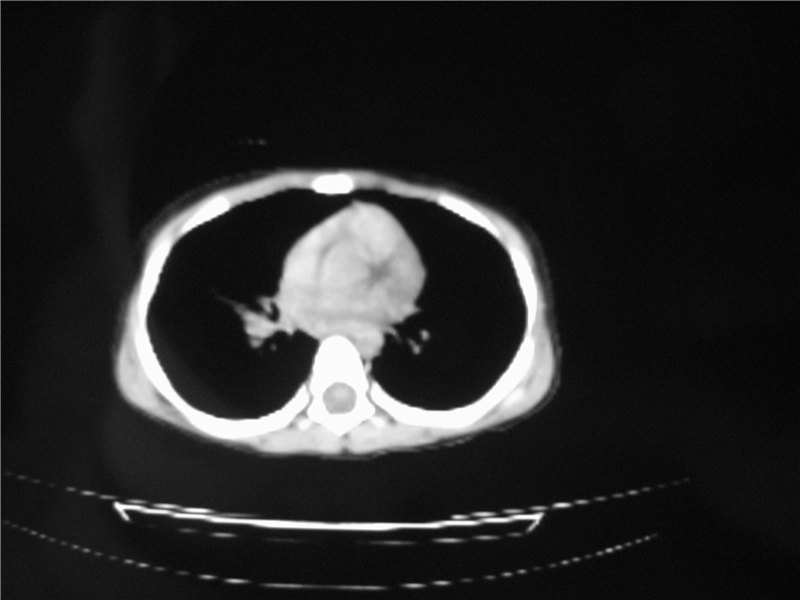

标题: PED3236:男2岁进食花生米后发烧10天。

右肺中叶及下叶内段大片实变密度增高影,可见支气管气象,肺炎.

摄吸气及呼气相对比片,本例为有肺中叶阻塞性炎症、不张,右肺下叶阻塞性炎症。

1)右肺炎症并右肺中叶肺不张,右肺上叶充气不良。2)右侧支气管异物不排除。

结合临床考虑支气管异物并阻塞性肺炎、肺不张。

右肺中叶及下叶内段大片实变密度增高影,可见支气管气象,肺炎.  ------异物阻塞所致!建议去除!